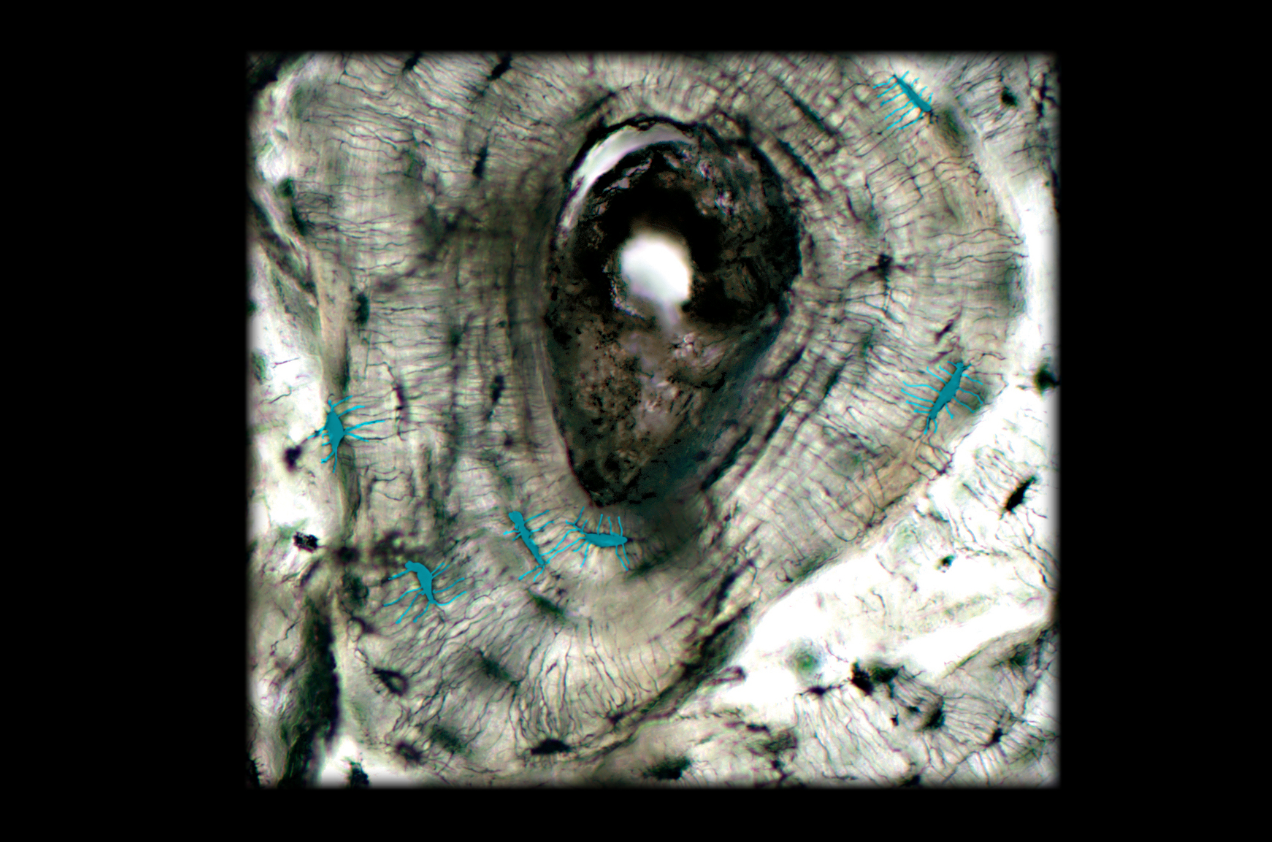

Osteon

19

New cards